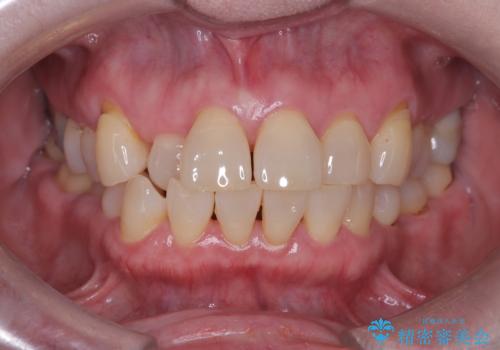

- 前歯の隙間とへこみが気になり、特に舌で触ると気になってストレスを感じるとのことで来院された患者様です。

上下ともに軽度の叢生があり、下顎がやや前突傾向にあったため、本来であれば矯正治療が第一選択となります。矯正によって下の前歯を後方に移動させることで、咬み合わせの改善とともに前歯のデコボコも整えることができます。

しかし、患者様はワイヤー矯正もマウスピース矯正も「絶対にしたくない」との強いご希望がありました。